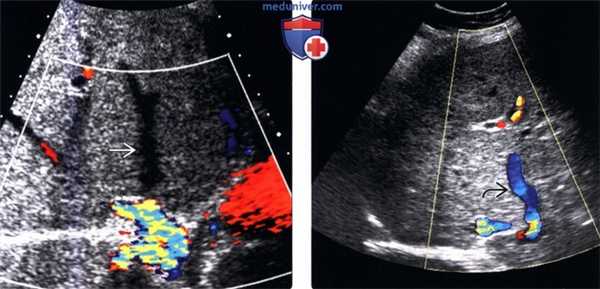

(Слева) На поперечной сонограмме (цветовая допплерография) печени у женщины 48 лет с известной истинной полицитемией, предъявляющей жалобы на боль в правом подреберье, с повышением функциональных печеночных проб, определяется отсутствие кровотока в правой долевой ветви печеночной вены.

(Справа) На сонограмме (цветовая допплерография) у этой же пациентки визуализируются крупные коллатеральные внутрипеченочные вены , обеспечивающие ток крови в обход «закрытых» печеночных вен.

4. УЗИ признаки синдрома Бадда-Киари:

• Цветовая допплерография:

о Печеночные вены и нижняя полая вена:

- Отсутствие кровотока в печеночных венах или отсутствие пульсации в них («плоский» спектр)

- Реверсивный кровоток в печеночных венах и НПВ

- «Двуцветное» окрашивание печеночных вен из-за наличия внутрипеченочных коллатералей

- Чувствительность: 87,5%

о Воротная вена:

- Медленный гепатофугальный ток крови со скоростью 11 см в секунду и меньше

о Печеночная артерия: индекс резистентности равен 0,75 или выше